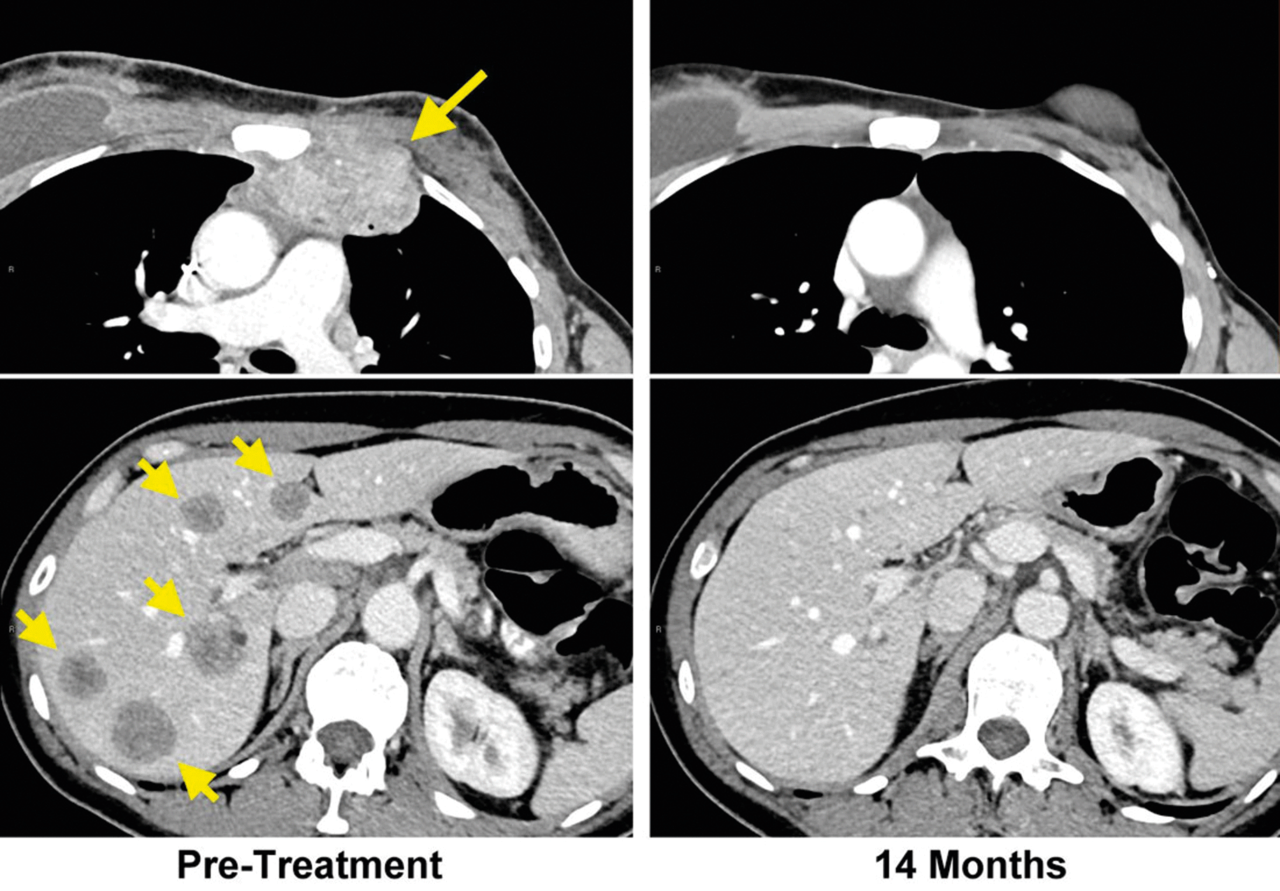

Im CT der Patientin sind die Filiae in der Brustwand (links) deutlich zu erkennen. 14 Monate nach der speziellen adoptiven Immuntherapie ist der CT-Befund unauffällig (rechts). Im CT der Patientin sind die Filiae in der Brustwand (links) deutlich zu erkennen. 14 Monate nach der speziellen adoptiven Immuntherapie ist der CT-Befund unauffällig (rechts). © National Cancer Institute

Sechs Wochen nach der Zellinfusion war die Tumorlast um 51 % zurückgegangen, nach einem Jahr konnten in der Bildgebung keine Läsionen mehr nachgewiesen werden. Weitere zwölf Monate später hatte sich an diesem positiven Ergebnis nichts geändert. Acht der elf infundierten T-Zell-Klone ließen sich 17 Monate nach der Behandlung noch im Blut der Patientin nachweisen, was auf eine dauerhafte Immunantwort hindeutet.

Im CT der Patientin mit chemotherapieresistentem, metastasiertem Brustkrebs sind die Filiae in Brustwand (links oben) und Leber (links unten) deutlich zu erkennen. 14 Monate nach der speziellen adoptiven Immuntherapie ist der CT-Befund unauffällig (rechts oben, rechts unten). Im CT der Patientin mit chemotherapieresistentem, metastasiertem Brustkrebs sind die Filiae in Brustwand (links oben) und Leber (links unten) deutlich zu erkennen. 14 Monate nach der speziellen adoptiven Immuntherapie ist der CT-Befund unauffällig (rechts oben, rechts unten). © National Cancer Institute